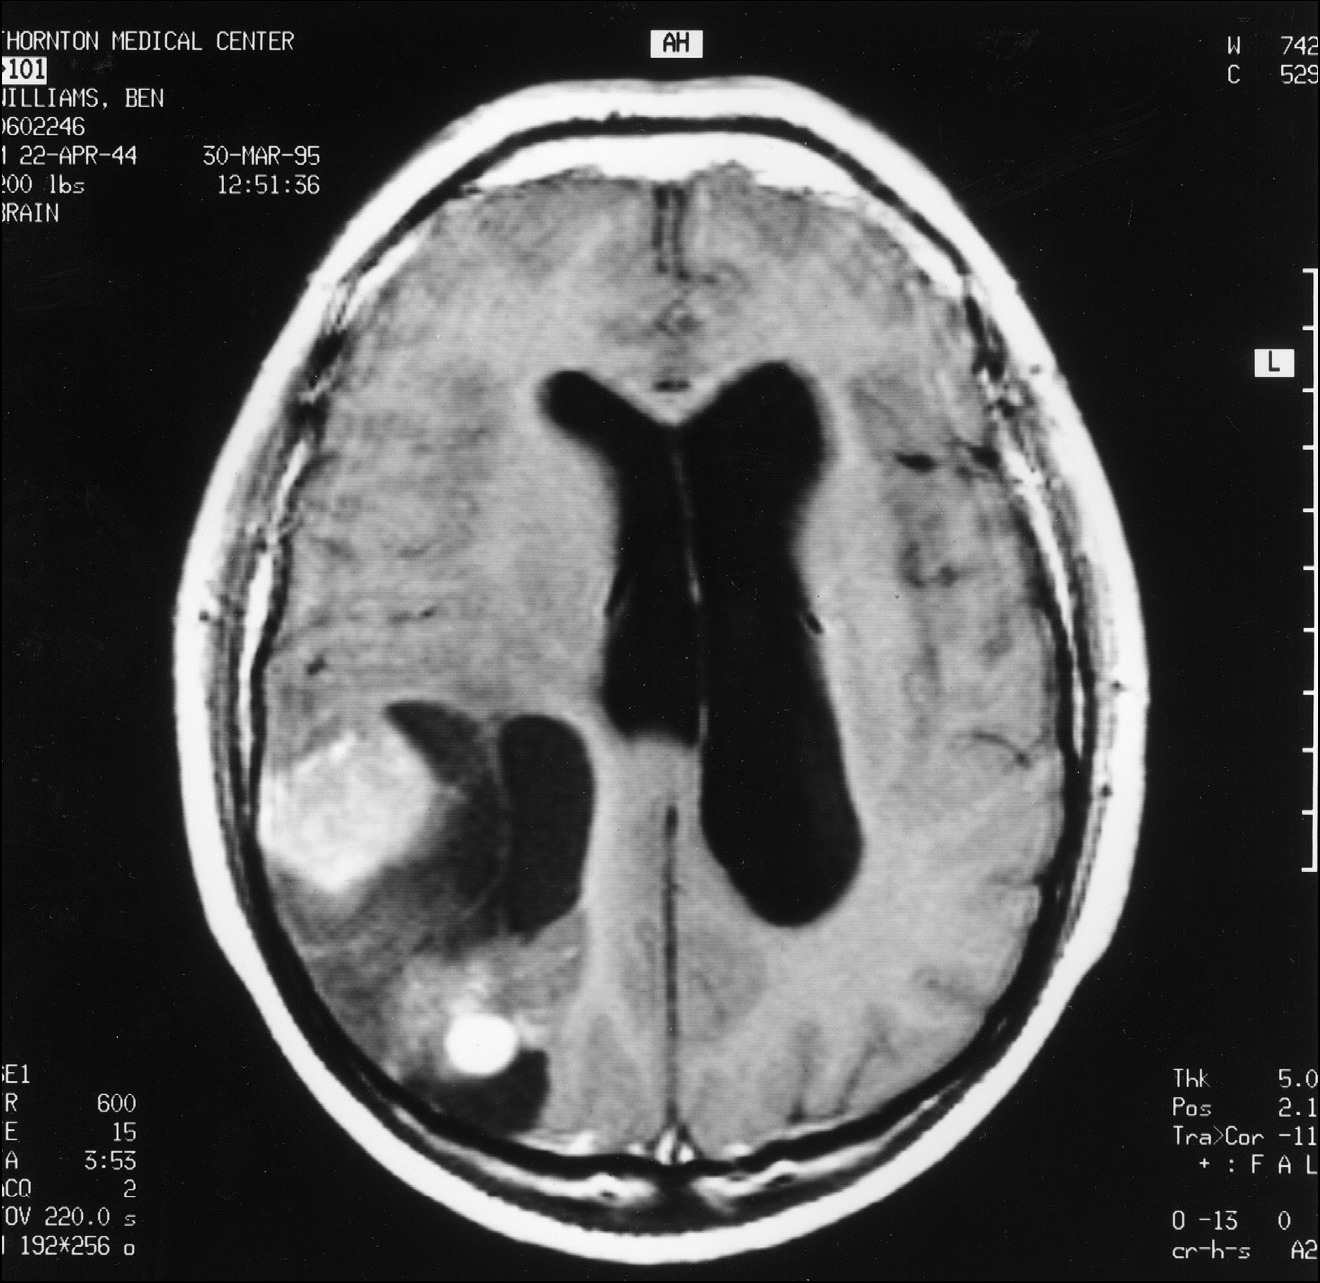

MRT pateikia smegenų skenavimų seriją, fiksuojančią smegenų pjūvius nuo viršaus iki apačios, iš šono į šoną ir iš priekio į galą. Šiam konkrečiam tyrimui visos trys serijos buvo pateiktos du kartus – vieną kartą prieš man gaunant gadolinio injekciją ir vieną kartą po jos. Gadolinis yra kontrastinė medžiaga, kurią absorbuoja naviko audinys, bet ne normalus smegenų audinys. Jei navikas yra, gadolinis MRT vaizde atrodo kaip ryškiai baltos dėmės; kuo ryškesnės dėmės, tuo sparčiau navikas auga. Tai taip pat parodo, kiek naviko yra.

Kai MRT pagaliau baigėsi, pradėjau rinkti savo daiktus, bet technikas Patrick pasakė, kad gydytojai norės mane pamatyti nedelsiant. Iš to supratau, kad jis skenavimo metu pastebėjo kažką labai rimto. Kai grįžau į priėmimo skyrių, rezidentas neurologas žiūrėjo MRT vaizdus monitoriuje. Jam akivaizdžiai buvo sunku pasiruošti pranešti blogą žinią, todėl vietoj to pakvietė mane kartu pažiūrėti į skenuotus vaizdus. Buvau priblokštas. Visa dešinioji smegenų pusė buvo naviko apimta (žr. čia ir čia). Akimirką atsigavęs, pakomentavau: „Bent jau dešinėje pusėje." Buvau matęs, kokie pražūtingi gali būti kairiojo pusrutulio pažeidimai. Neurologas pritarė mano pozityviam požiūriui, tačiau buvo aišku, kad, jo manymu, netrukus mirsiu.

1 pav.

MRT pjūvis, atliktas per smegenų vidurį tarp priekio ir galo.

2 pav.

MRT pjūvis, atliktas per smegenų vidurį tarp viršaus ir apačios. Panašūs naviko kiekiai buvo matomi bent pusėje abiejų serijų pjūvių.

Matyt, tokie dideli ir grėsmingi smegenų navikai kaip manasis yra reikšmingas įvykis. Netrukus pusė neurologijos skyriaus susirinko apžiūrėti vaizdų. Mano neurochirurgas apibūdino naviką kaip didelio apelsino dydžio; mano neuroonkologas vėliau apskaičiavo jo tūrį – 184 kubinius centimetrus.